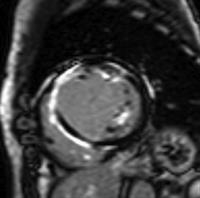

参:19歳の症状のないバスケットプレーヤーで症状がなく、心電図変化を認める症例のMRI画像の変化を示す。Baselineでは14mmの後中核壁の肥厚を認めるのみであったが、三か月後の運動中止では心筋壁の変化は認めなかった。造影MRIを行ったところ遅延造影が軽度肥厚した心筋の局所に認められ、肥大型心筋症と診断された。

参:肥大型心筋症の肥大パターンを見てみると下図のようになる。